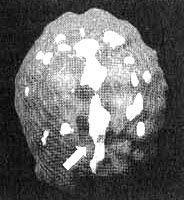

Мозг Бетси - чрезмерная фиксация

Трехмерное изображение - активный мозг, вид сверху. Обратите внимание на выраженное повышение активности